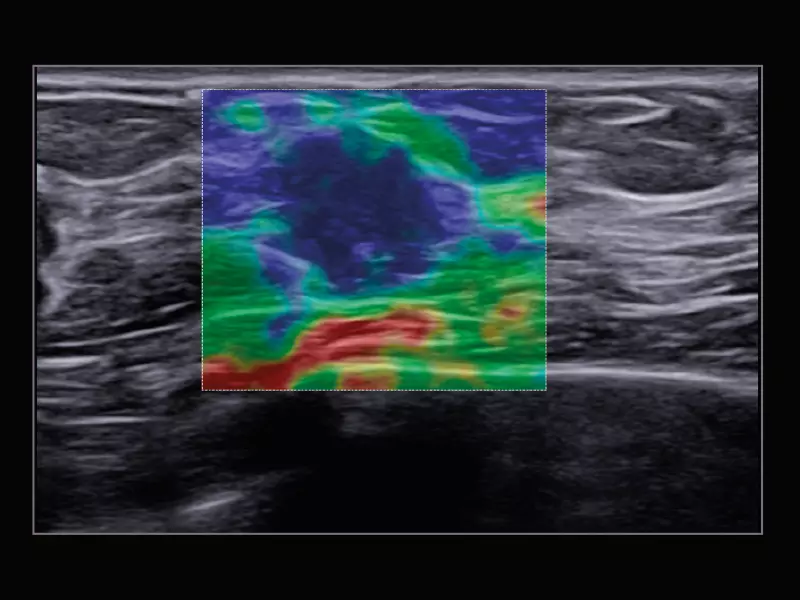

MyLab™C30 - SWE breast

MyLab™C30 - SWE breast